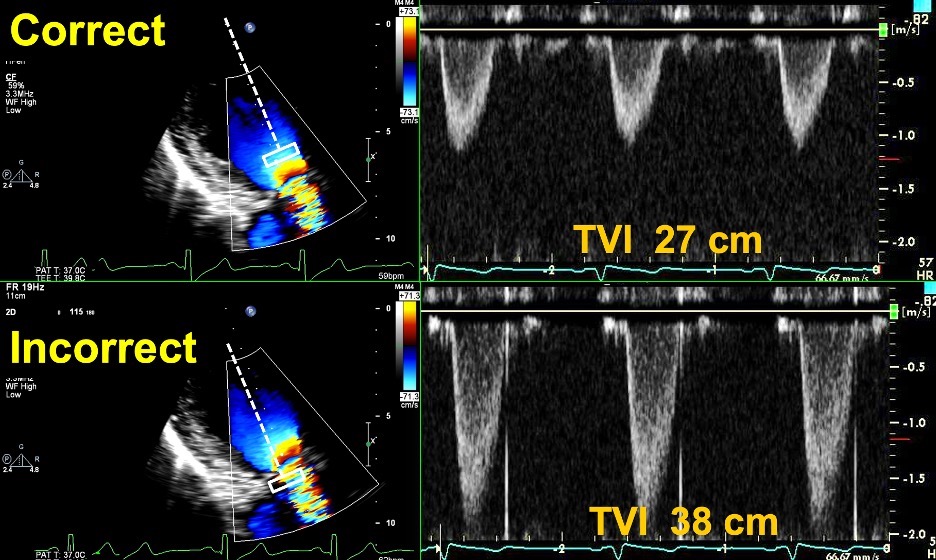

Fig. 6.Correct and Incorrect method of measuring the TVI of the LVOT. Top Images: Pulse Wave Doppler with sample volume placed immediately proximal to the zone of flow acceleration within the LVOT, with an accurate TVI of 27 cm. Bottom images: Pulse Wave Doppler with sample volume placed within the zone of flow acceleration leading to a spuriously elevated TVI of 38 cm. This can lead to an elevated DVI in a patient with an obstructive prosthesis, and care should be taken to avoid this error.